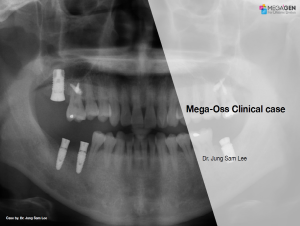

Keywords

e.g. product name, treatment solution, author, clinician name